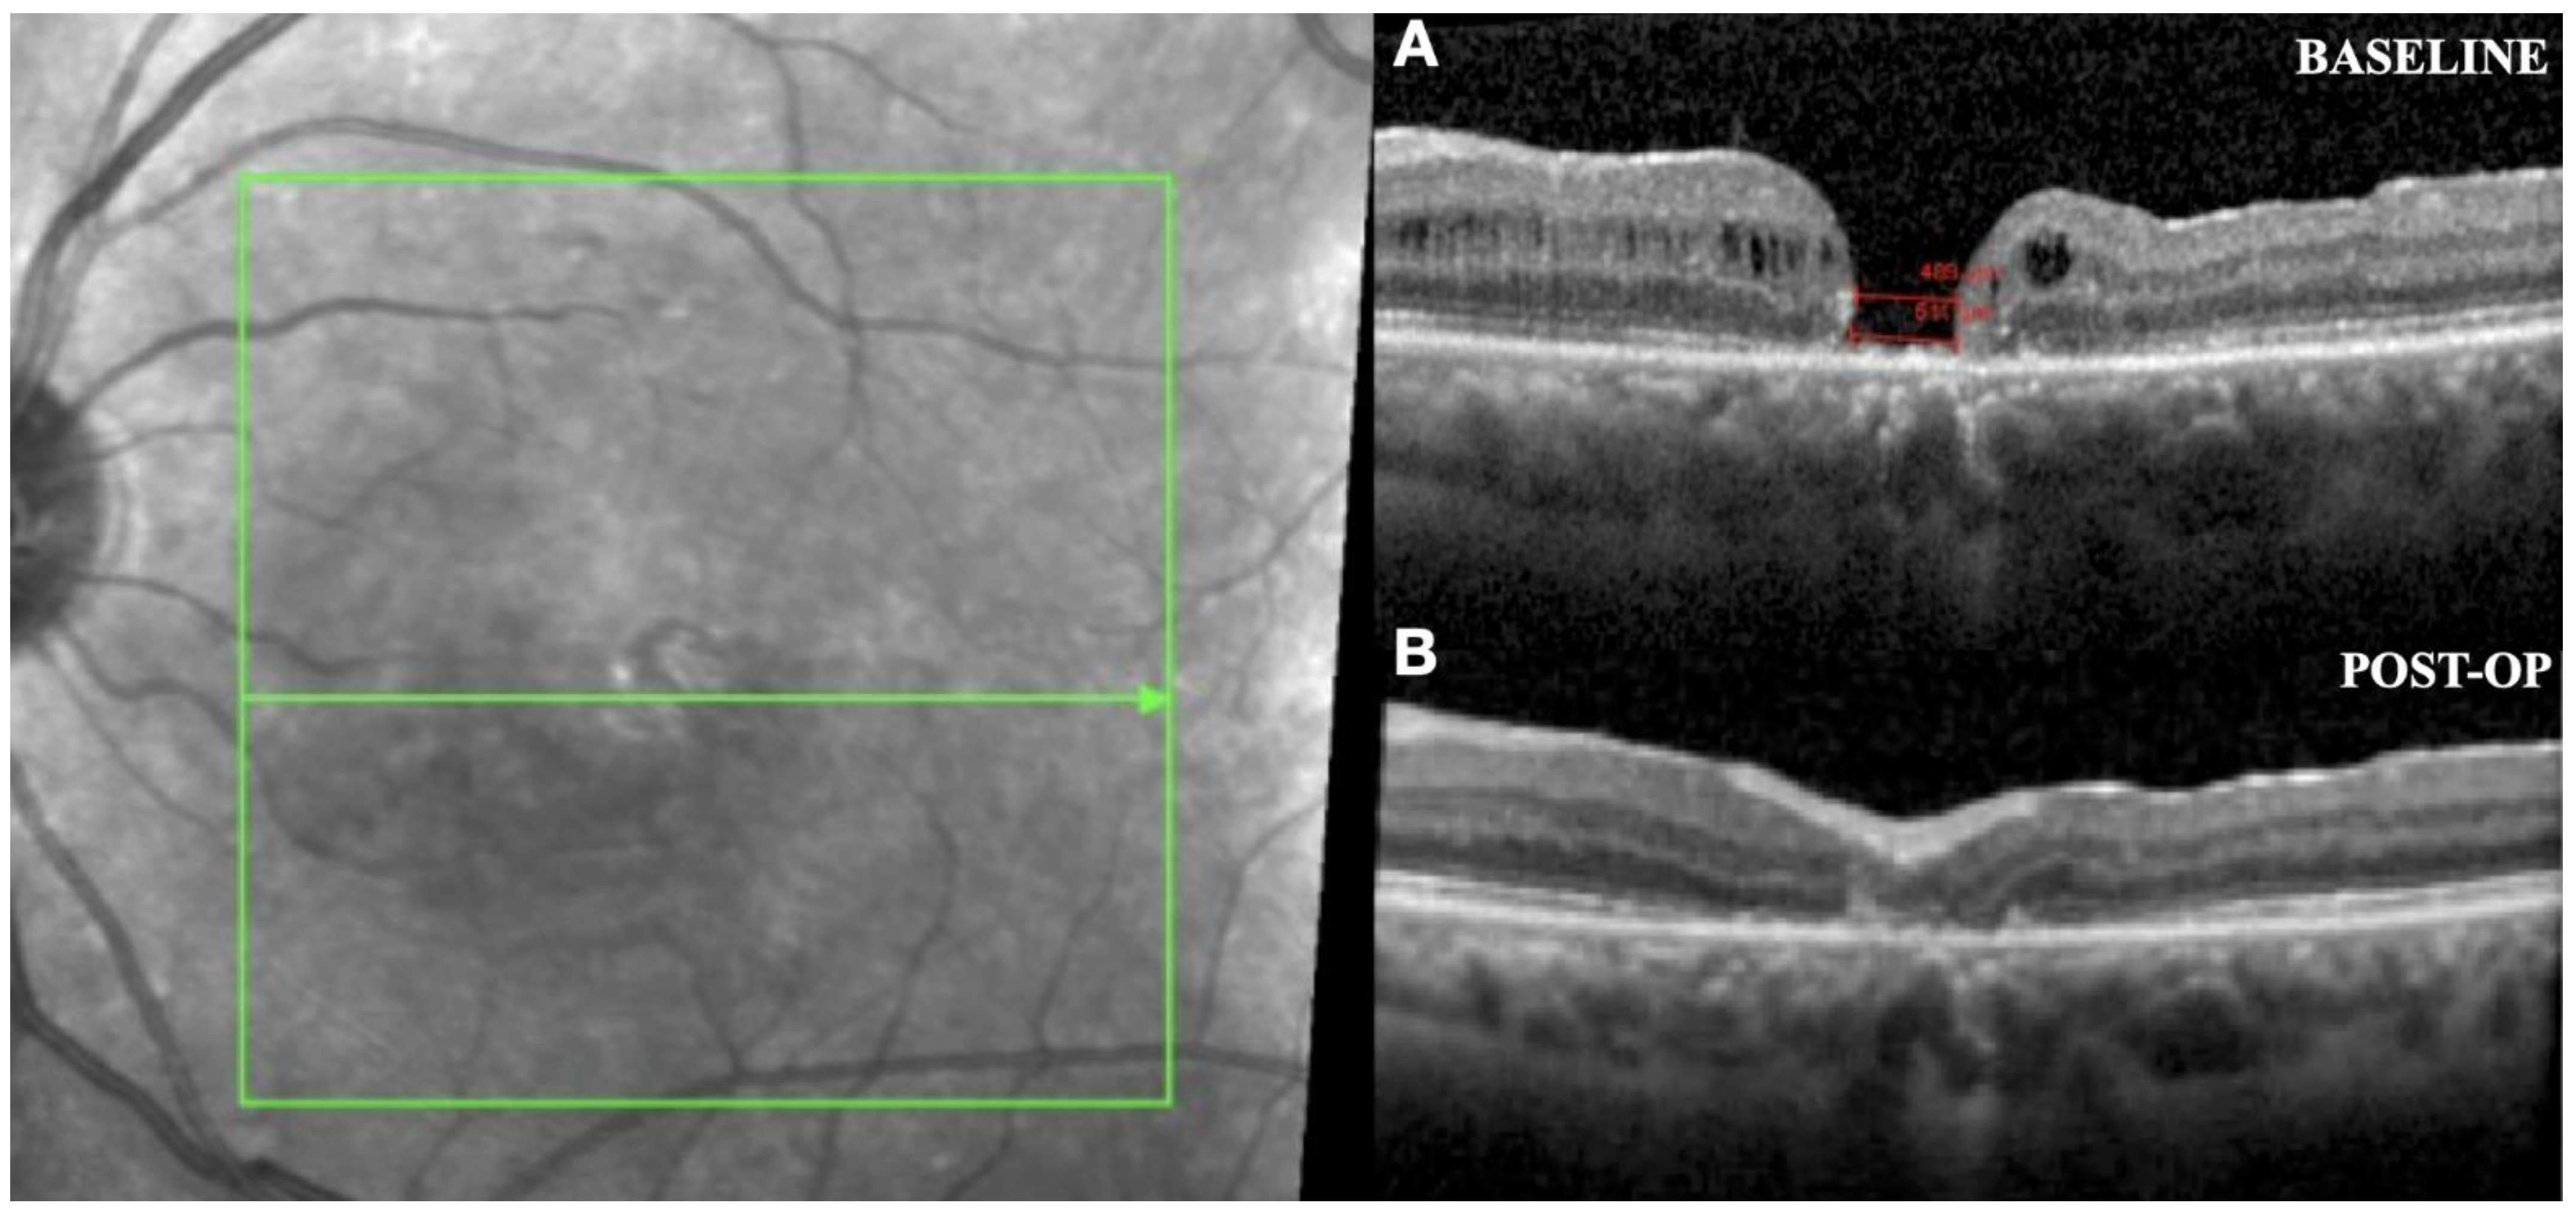

2.7. Intraoperative OCT

2.8. New Instrumentation in Vitreoretinal Surgery